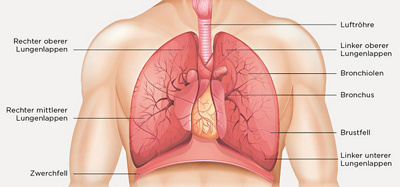

Bei einem sogenannten «Fleck» auf der Lunge handelt es sich um einen Gewebeherd, der gut- oder bösartig sein kann. Statistisch gesehen sind bösartige Herde in der Lunge viel häufiger als gutartige, weshalb unklare Herde weiter abgeklärt werden müssen.

Als Erstes wird eine Computertomographie (CT) des Brustkorbes erstellt und eine flexible Bronchoskopie (Spiegelung der Luftröhre und der Bronchien) durchgeführt. Die CT erlaubt es, den Herd in der Lunge genau zu lokalisieren und die Beziehung zu den umgebenden Strukturen (Herz, Gefässe, Bronchien, Luft- und Speiseröhre) genau zu analysieren. Mit der ambulant durchgeführten Bronchoskopie des Pneumologen gelingt es meist, die Diagnose durch eine Gewebeprobe zu sichern. Je nach Lage des Herdes kann zur histologischen Klärung auch eine CT-gesteuerte Probeentnahme durch den Radiologen nötig sein.